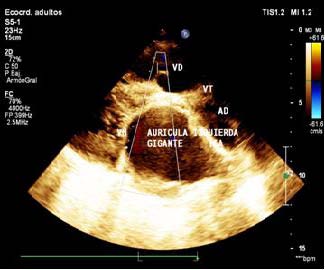

Se procede a realizar Ecocardiograma Transtorácico usando equipo Philiph IE 33: donde se encontró una aurícula Izquierda remodelada, un ventrículo izquierdo con disminución de su cavidad. Cavidades derechas (CD) con aumento significativo de sus diámetros y disfunción sistodiastólica. Estimación de Presiones Pulmonares de 75 mm/Hg. (Imágenes 1, 2 y 3)

Imagen 1. Eje corto paraesternal izquierdo para visualizar válvula mitral, aurícula izquierda gigante y cavidades derechas.

VM: Válvula mitral - TIA: Tabique interauricular - AD: Aurícula derecha - VT: Válvula Tricuspídea - VD: Ventrículo derecho.